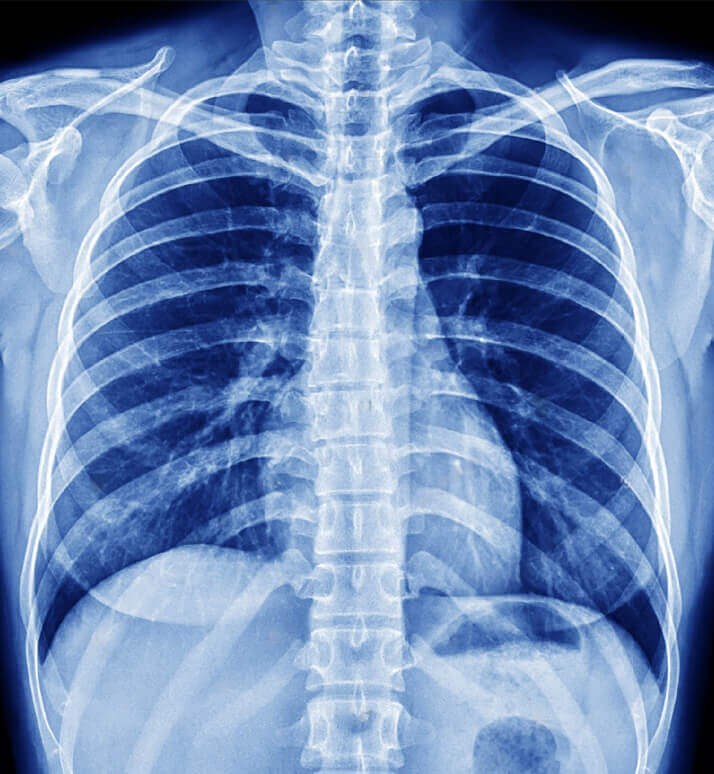

Digital Xray

Digital X-ray is an advanced imaging technology that uses electronic sensors to capture images of the inside of the body.